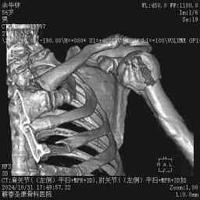

肱骨近端骨折

肱骨近端骨折...